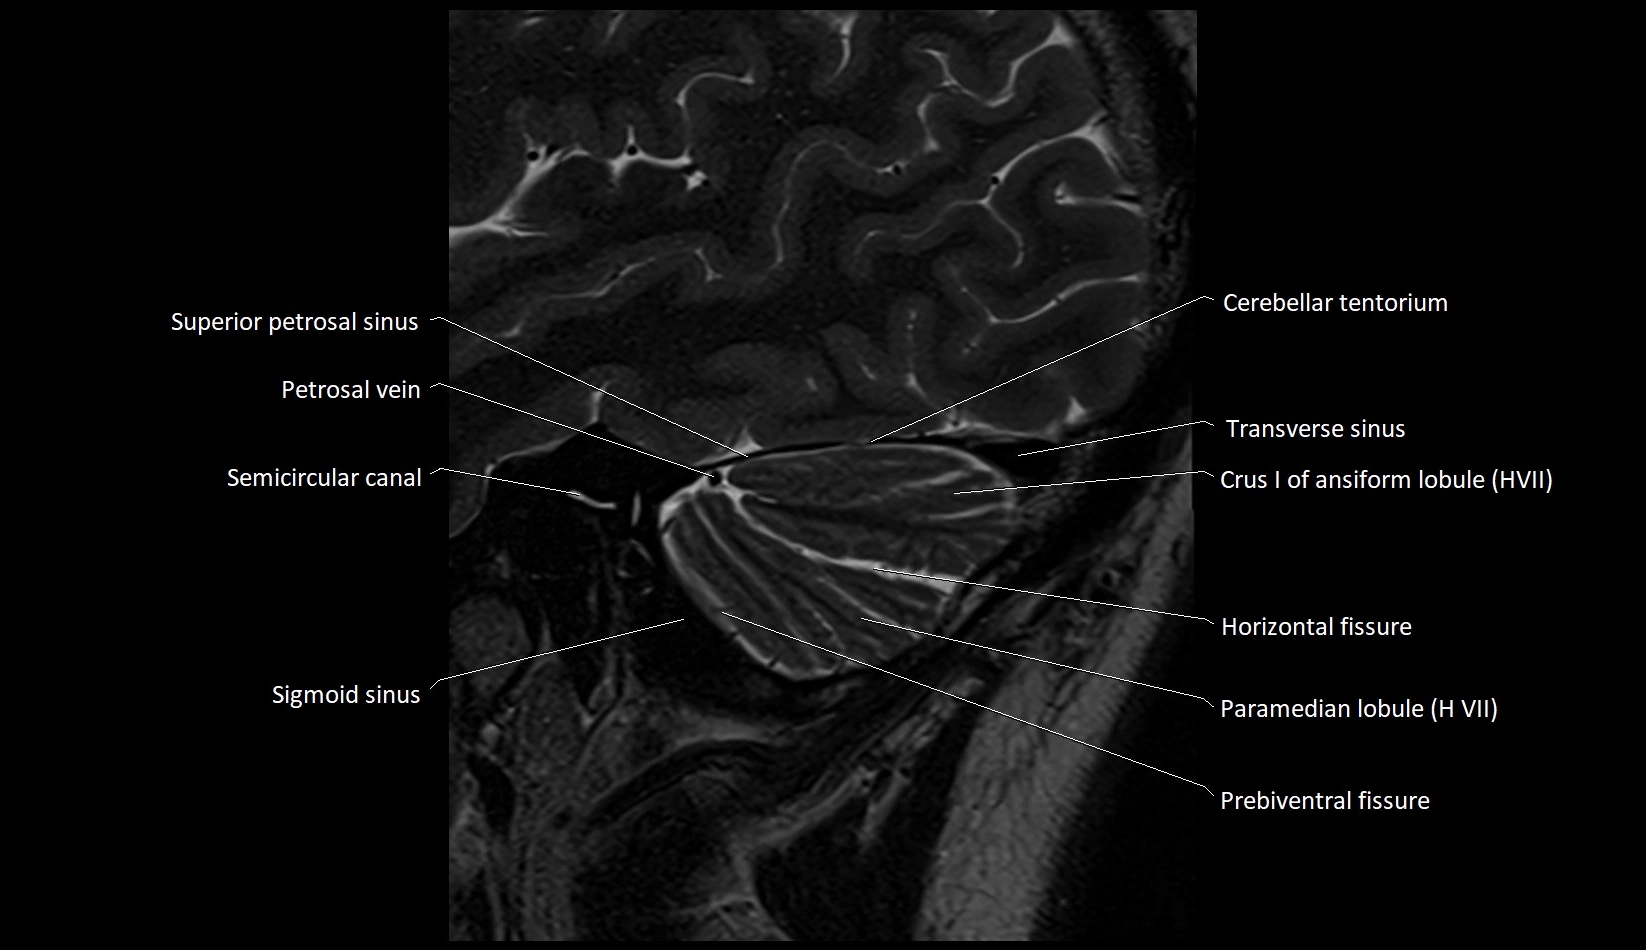

MRI images